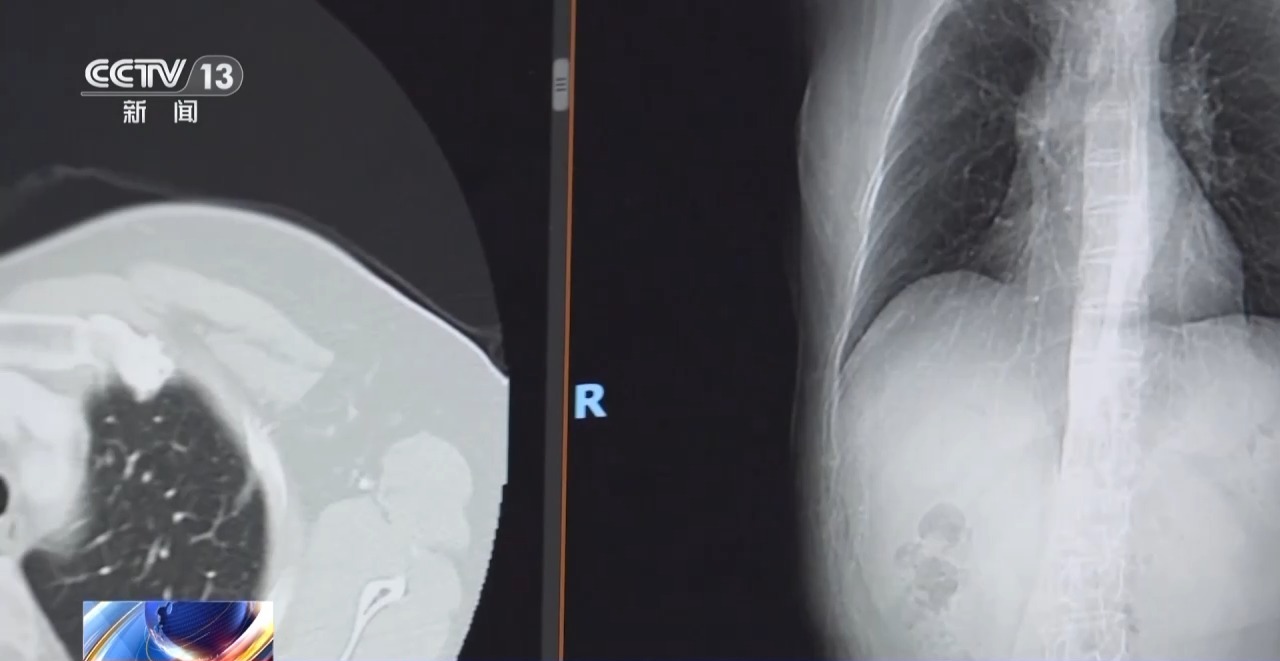

今天至4月21日是第31个全国肿瘤防治宣传周,世界卫生组织下属的国际癌症研究机构(IARC)最新数据显示:肺癌目前是全球发病率和死亡率均排名第一的癌症,肺癌连续十年位居全球癌症死亡率首位。

专家表示,对大多数筛查发现的磨玻璃样小结节要谨慎解读,它生长得非常缓慢,可以给它一定的冷静期进行观察,不建议过度治疗。

随着我国医学进步,肺癌患者的治疗有明显突破,磨玻璃样结节的肺癌,5~10年的生存率接近百分之百,实性肿块一期肺癌的5年生存率约为70%~80%。